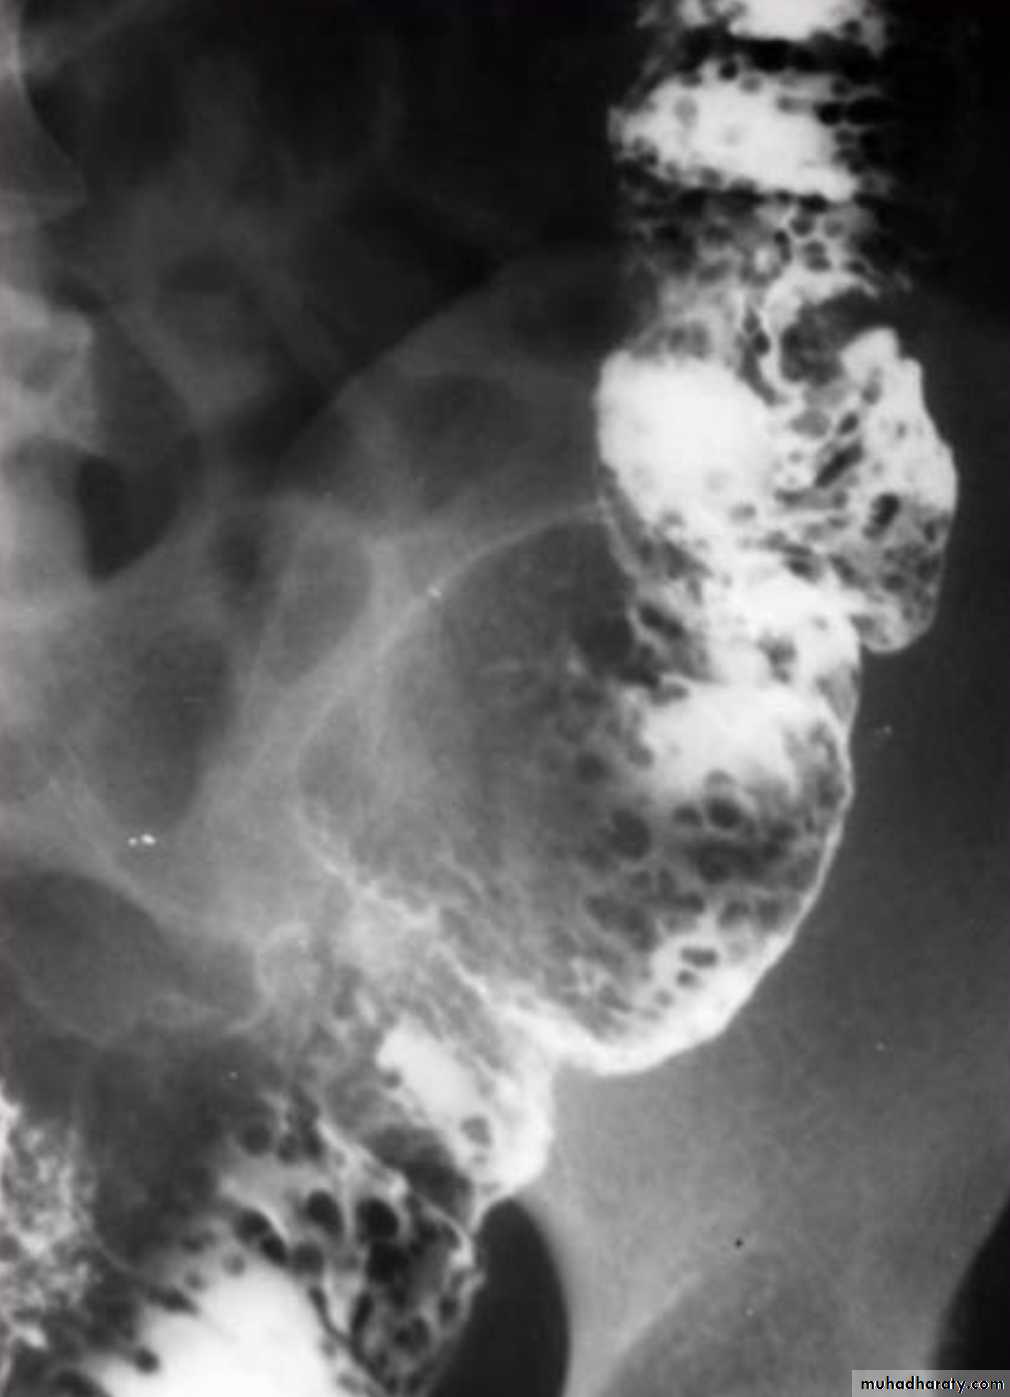

Barium small bowel follow-throughfindings of CD

Multiple mucosal ulcers aphthous ulcerslongitudinal fissures

Multiple skip lesions

when severe leads to cobblestone appearance

may lead to sinus tracts and fistulae

widely separated loops of bowel due to fibro-fatty proliferation

thickened folds due to edema

Pseudo diverticula formation: due to contraction at the site of ulcer with ballooning of the opposite site